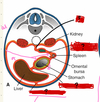

how does the development of the stomach affect the final positions of the foregut?

the rotation of the stomach pulls the mesenteries, omenta and peritoneal ligaments which pull the organs. some of theses organs (pancreas and duodenum) are pushed into the posterior abdominal wall and become retropeitoneal. Less sac is formed